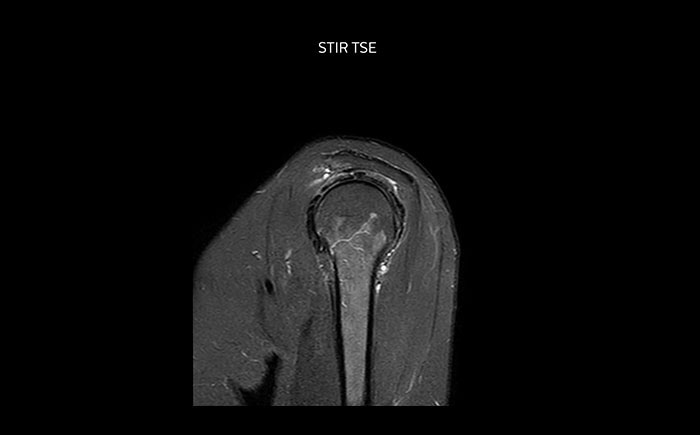

Shoulder MRI with high quality, large coverage

The Prodiva shoulder coil is very flexible and has large coverage, which makes good positioning easier, and that contributes to the superb image quality and high SNR that we get in our shoulder exams.

Shoulder MRI with high quality, STIR TSE

Scan time 2:50 min, FOV 160 mm,

acq voxels 0.70 x 0.99 x 3.0 mm.